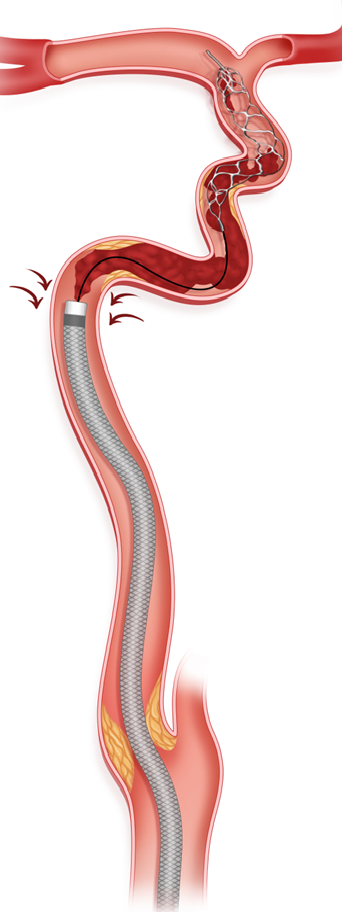

造影见左侧颈内动脉再通,恢复血流,前向血流良好,但血管管腔可见血栓。在微导丝及微导管引导下通过8F导引导管送入0.058inch 115cm 中间导管到位后,开始抽吸血栓,未见明显血栓抽出,给予替罗非班(6ml/h)。

造影可见颈内动脉C1段仍有狭窄,退出中间导管,在8F导引导管内沿5.0*35mm Syphonet®取栓支架导丝植入一枚Wallstent支架(9.0*50mm)。

再次造影时发现最狭窄处狭窄改善不满意,再经5.0*35mm Syphonet®取栓支架导丝引导下送入2.5*20mm Emerge球囊,在支架内给予球囊扩张。

最后将8F导引导管撤至左侧颈总动脉,造影可见左侧颈内动脉血流通畅,前向血流III级,远端各分支显影良好。

补充步骤:在球囊扩张过程中如发现栓子负荷大,可将血栓抽吸导管反复抽吸清理血栓。

持续负压下前进血栓抽吸导管,反复抽吸,清理闭塞管腔内的血栓。如果造影发现Syphonet®取栓支架内捕获了脱落的血栓,则回撤Syphonet®取栓支架,清理支架内血栓。